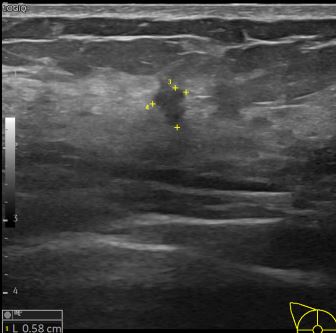

상기환자는 우측 겨드랑이 부어있어 내원하신40대초반

여성분으로 의심스러운 우측혹 조직검사 시행해 유방암 으로 진단되었습니다